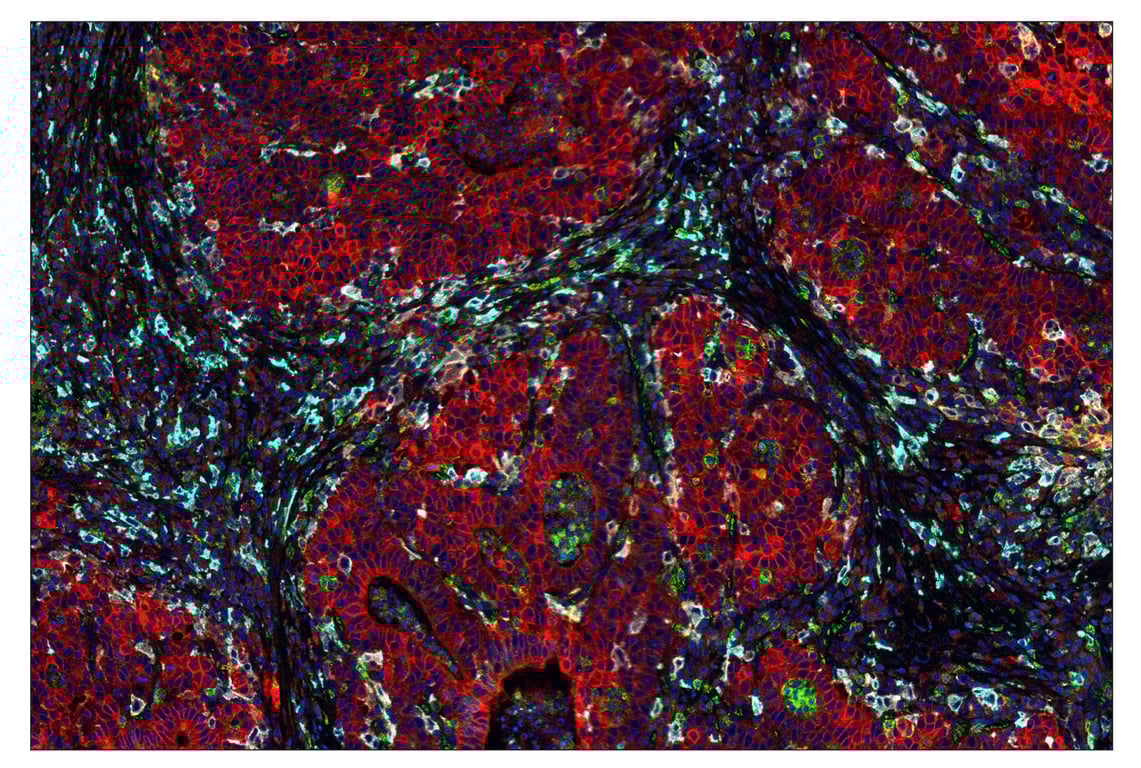

SignalStar™ multiplex immunohistochemical analysis of paraffin-embedded human gastric adenocarcinoma using CD163 (D6U1J) & CO-0022-594 SignalStar™ Oligo-Antibody Pair #43547 (magenta), Tox/Tox2 (E6I3Q) & CO-0016-488 SignalStar™ Oligo-Antibody Pair #31189 (green), α-Smooth Muscle Actin (D4K9N) & CO-0024-647 SignalStar™ Oligo-Antibody Pair #63902 (red), and Pan-Keratin (C11) & CO-0003-750 SignalStar™ Oligo-Antibody Pair #97227 (cyan). All fluorophores have been assigned a pseudocolor, as indicated. Staining was performed on the BOND RX by Leica Biosystems.

Immunohistochemistry Image 7: CD163 (D6U1J) & CO-0022-594 SignalStar<sup>™</sup> Oligo-Antibody Pair